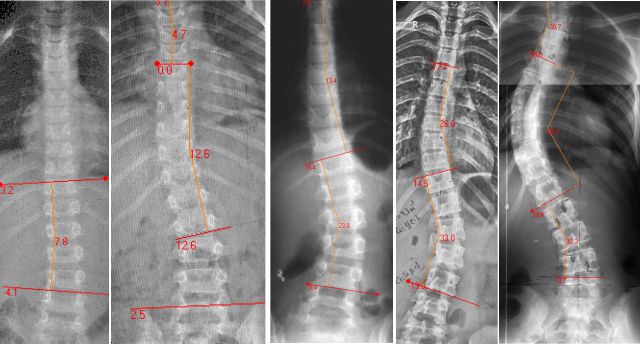

Рентген поясницы: анатомические особенности и медицинские исследования

Раздел: Фотоэссе